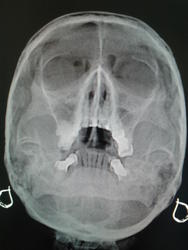

Пол пациента: Женский пол Тип патологии: Другое Область исследования: Челюстно-лицевая область и шея Методы исследования: Rg Женщина 1960 г.р,направлена лором на флг пазух носа.Стоит ли в данном случае писать кисту гайморовой пазухи справа? ID:37375 Пнд, 21/04/2014 - 21:08 #1 И.Бондаренко Не на сайте Был на сайте: 3 дня 10 часов назад Зарегистрирован: 13.09.2011 - 22:55 Публикации: 9206 Не очень на кисту похоже. Возможно зуб или остеома. Сделайте боковой снимок. Пнд, 21/04/2014 - 23:30 #2 OPEXOB Не на сайте Был на сайте: 9 лет 11 месяцев назад Зарегистрирован: 26.07.2008 - 10:02 Публикации: 280 Не сильно ли "задрали" голову? В данных случаях выполняют гайморографию с контрастированием или КТ или МРТ. Чт, 24/04/2014 - 21:24 #3 JJ Не на сайте Был на сайте: 11 лет 5 месяцев назад Зарегистрирован: 03.04.2014 - 20:35 Публикации: 102 И.Бондаренко wrote: Не очень на кисту похоже. Возможно зуб или остеома. Сделайте боковой снимок. +1

Не очень на кисту похоже. Возможно зуб или остеома. Сделайте боковой снимок.

Не сильно ли "задрали" голову?

В данных случаях выполняют гайморографию с контрастированием или КТ или МРТ.